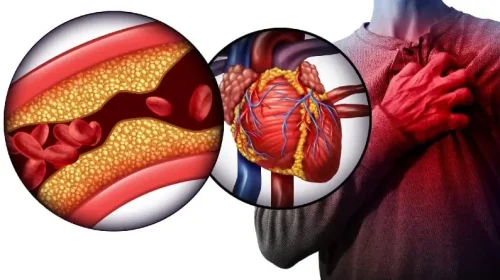

Heart Plaque

Plaque is made up of deposits of fatty substances, cholesterol, cellular waste products, calcium, and fibrin.

Coronary Heart Disease

A disease in which there is a narrowing or blockage of the coronary arteries (blood vessels that carry blood and oxygen to the heart).